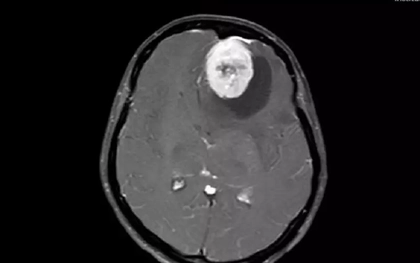

Khối u khổng lồ đẩy lệch não ẩn sau những cơn đau đầu

Những cơn đau đầu dai dẳng đã che giấu khối u khổng lồ gần 8cm trong não bệnh nhân. Khi nhập viện, người bệnh đã yếu hai chân, rối loạn vận động do não bị chèn ép, đẩy lệch sang một bên. -